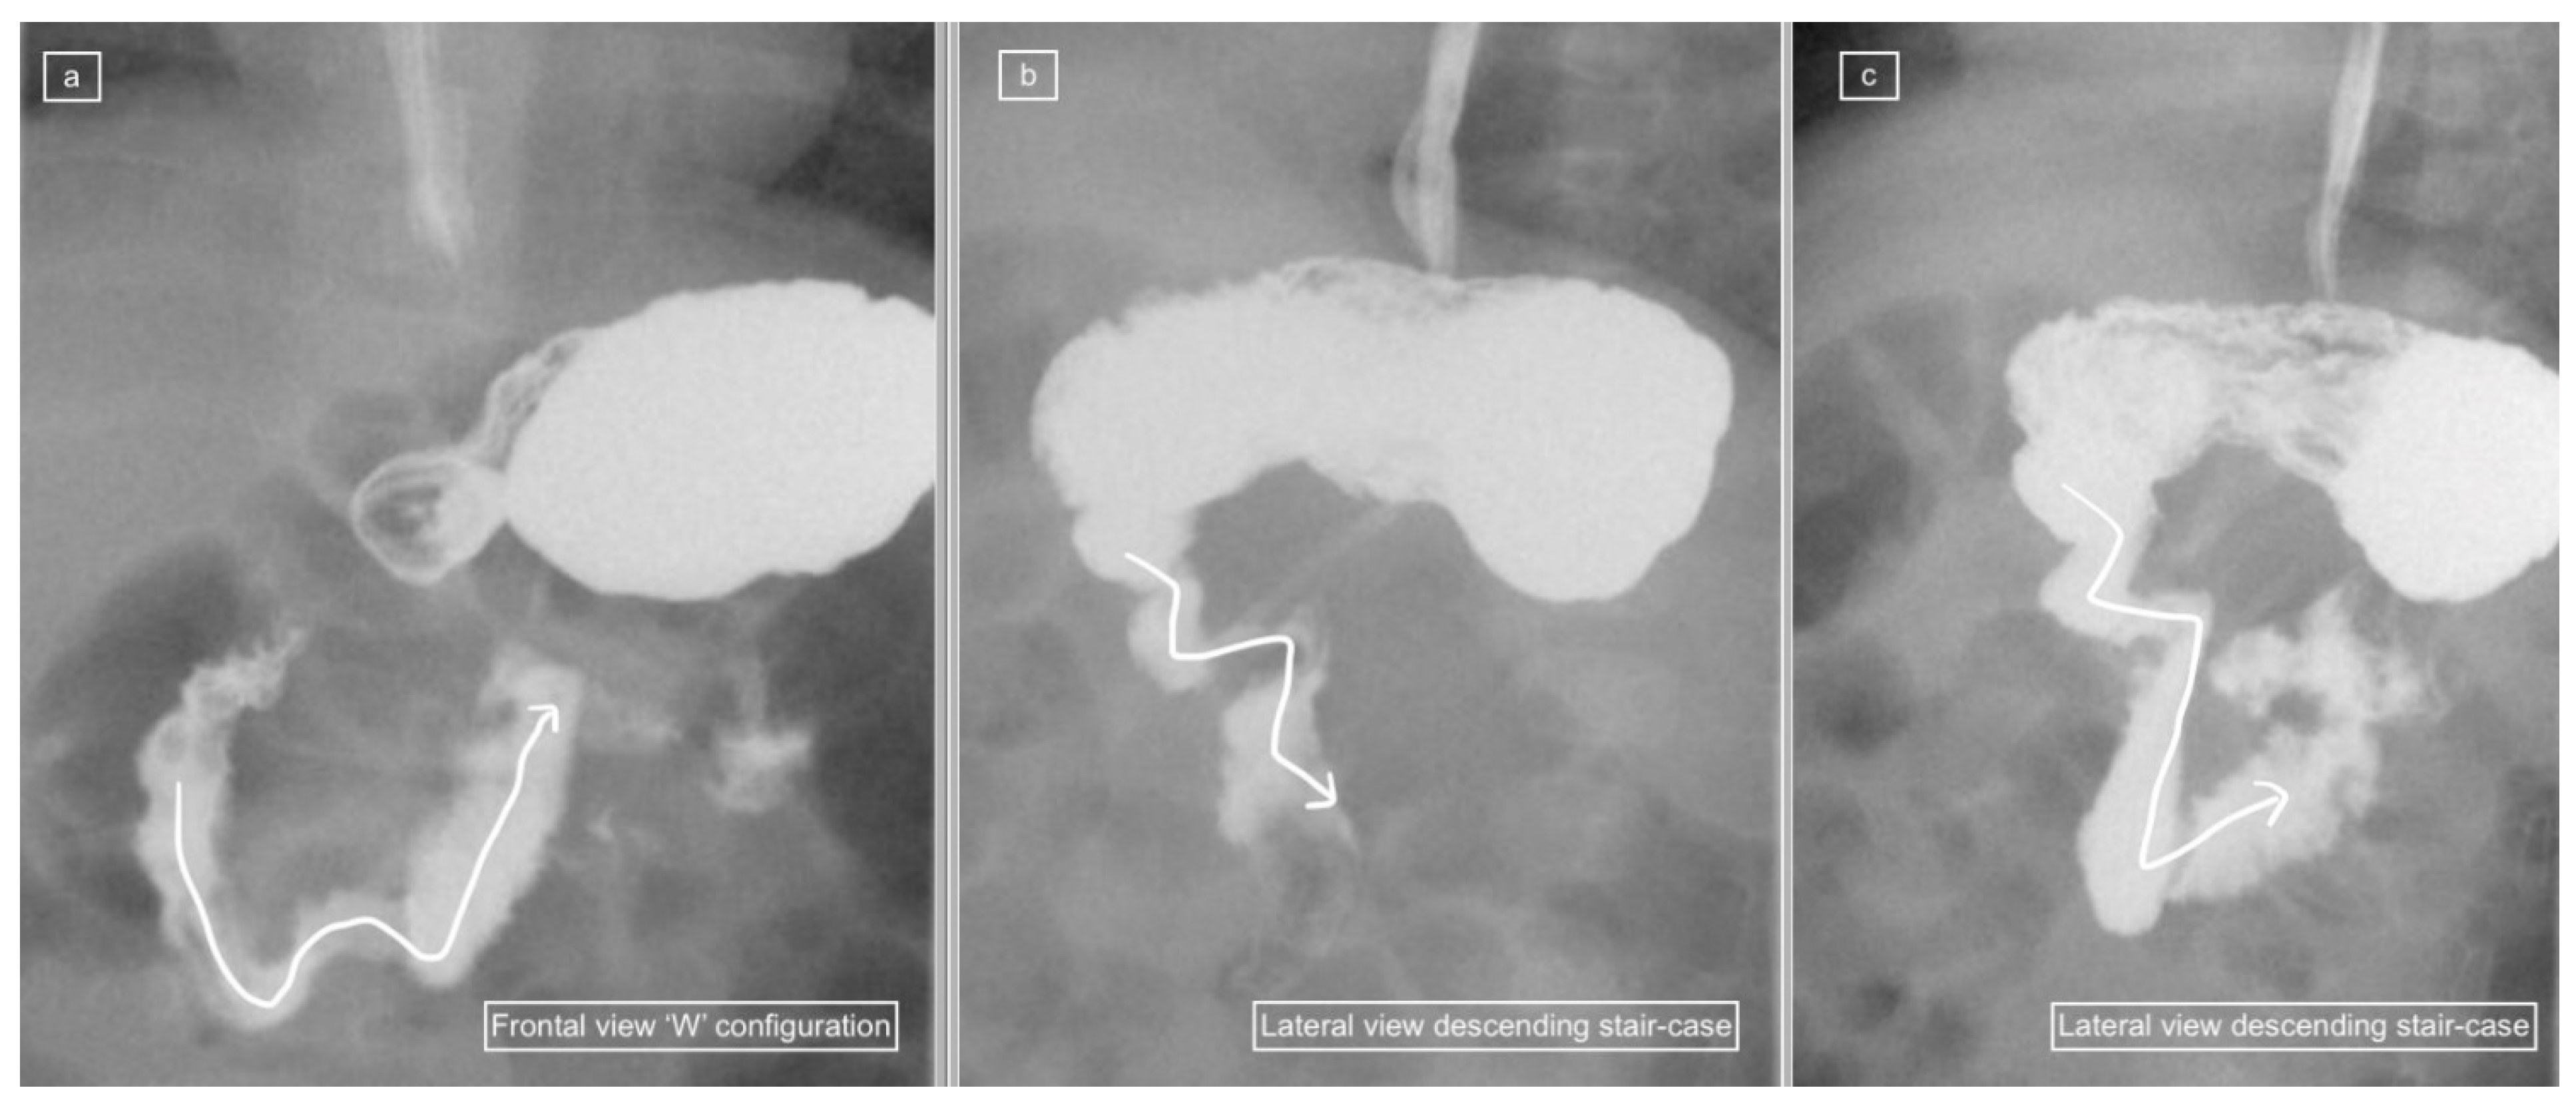

The recorded images of the lateral view or cine loops, including the lateral position, were reviewed independently before a review of findings on the frontal (AP) view. Studies were categorized as having ”not captured” or ”inadequately captured” (available but uninterpretable due to inadequate luminal contrast outlining the duodenum on the view) images of the lateral view. We calculated the proportion of studies with adequate lateral views (by excluding the non-captured and inadequately captured cases), and only studies designated to have an adequate lateral view were evaluated further regarding the configuration of the duodenum. This latter subset was then categorized as ”normal”, ”descending staircase”, or abnormal from the lateral view. The descending staircase sign was defined as a stepwise inferior descent of the duodenal course from D1 through D2 oriented posteriorly, after which D3 and D4 ascend in the retroperitoneal position, leading up to the duodeno-jejunal flexure at the same height as D1, before coursing anteriorly (Figure 2, Figure 3 and Figure 4).

A total of 18 of the 26 adequate lateral UGI exams (69%) were interpreted as normal, 7/26 (27%) were interpreted as demonstrating the descending staircase configuration (Figure 2, Figure 3 and Figure 4) and 1/26 (4%) was interpreted as abnormal (Figure 5).

Comparison with the AP view was performed (summarized in Figure 6) which demonstrated 2 abnormal exams (1 malrotation and 1 non-rotation), 6 duodenum redundum and 18 normal studies.

Six of the seven lateral views with descending staircase duodenums had duodenum redundum on the AP view and one was reported as normal, but on review contained a naso-jejunal tube in situ, causing distortion of the duodenal anatomy and spasm of the bowel (Figure 7). The single abnormal lateral duodenum was confirmed on AP as a non-rotation (Figure 5). There was one patient with a normal lateral view but malrotation on the frontal view (Figure 8).

Despite the relatively frequent occurrence of duodenal redundancy reported (29% in the study by Sizemore et al. [15]), neither these authors nor any of the other papers reporting and promoting the use of the lateral view refer to the appearance of duodenal variants on lateral views, and whether these cause diagnostic dilemmas such as false positive diagnoses of malrotation. Clinical radiologists should be able to recognize normal variations in order to avoid overdiagnosis of malrotation, resulting in unwanted surgery. We demonstrated a frequency of 23% duodenal variants in our patient population and all of these (100%) demonstrated a characteristic descending staircase sign on the lateral view. However, one case designated as having a descending staircase sign on the lateral view showed a normal duodenum on the frontal view and on review, there is a clear distortion of the duodenum caused by an indwelling naso-jejunal tube with spasm of the bowel. This pitfall is a known potential diagnostic pitfall on the frontal view, which causes malposition of the DJ flexure but is not well documented in the lateral view.

The likely reason that most radiologists do not like to delay the duodenal roll in order to acquire an adequate lateral view is that the delay risks compromising the AP view—reflected by the low rate of adequate lateral views—26% in our sample and 55% in the Koplewitz et al. study [10]. A combination of the lateral view with an AP view can be complementary in supporting the correct diagnosis, with avoidance of ”false positives” and unnecessary surgery. As Long et al. have concluded previously for the frontal view and now shown again for the lateral view, false positives can be avoided by recognizing the variants of normal duodenum [17]. In addition to our recommendation of using the lateral view in conjunction with an AP view for diagnosis, we also recommend (a) an assessment of the lateral view quality before making conclusions, (b) caution when there are indwelling enteric tubes and (c) awareness of the descending staircase sign of duodenum redundum, which represents a variation of normal rather than pathology.